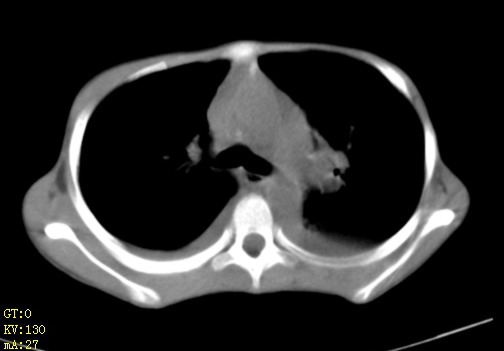

女,12岁,气促、咳嗽2天,3个月前查胸片示:两肺感染,急诊入院查ct,血常规等未检查。

1、左心房、左心室增大,考虑左心衰, 2、肺水肿合并感染 3、双侧胸腔积液

双肺中下野不规则片絮状阴影,中外带明显,双侧胸腔少量积液,心影增大,心腔密度减低,隆突下及左侧气管旁见钙化淋巴结影,考虑双肺感染、心衰;建议结合临床除外h1n1并急性心衰,先心不能排除。

两肺多发片絮状模糊影,以下肺外带居多,内见支气管气像,纵膈窗未减影,两侧胸腔积液,心影增大,结合心超,支持重症肺炎,非常时期,甲型h1n1流感不排除。